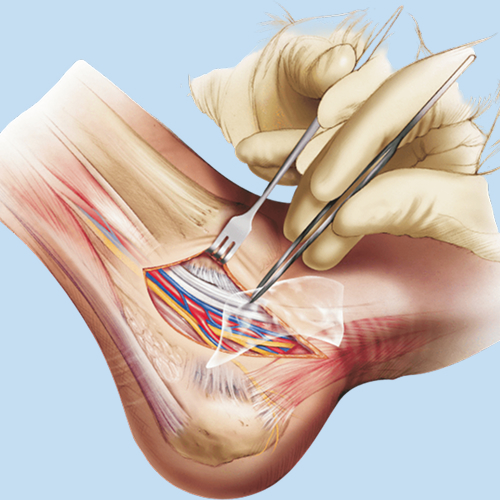

Biológicos Cirugía Cirugía Plástica y Craneomaxilofacial Columna Neurocirugía Ortopedia